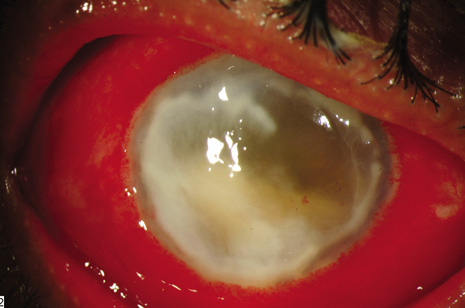

In this endophthalmitis category, patients may present weeks to months after cataract extraction, often with mild-to-moderate inflammatory signs and a chronic indolent course.16,94 P. acnes, a gram-positive, anaerobic pleomorphic rod, is a common causative organism in this category. The clinical P. acnes syndrome of delayed-onset pseudophakic endophthalmitis, first described by Meisler and associates94 in 1986, typically includes granulomatous inflammation with large keratic precipitates (Fig. 6) and a white intracapsular plaque that has been shown to be composed of organisms mixed with residual lens cortex. When infection with this slow-growing organism is suspected, anaerobic cultures of both the aqueous and vitreous should be obtained and held at least 2 weeks.

Fig. 6. Delayed-onset pseudophakic endophthalmitis. Left: This patient presented with granulomatous uveitis, vitritis, and a white plaque within the capsular bag, which is characteristic of infection caused by Propionibacterium acnes. Right: Marked granulomatous keratic precipitates are occasionally seen in endophthalmitis caused by P. acnes.

In a review of 19 patients with delayed-onset pseudophakic endophthalmitis (defined as those cases diagnosed 6 weeks or more after cataract surgery and excluding filtering bleb-associated cases), four different etiologic organisms were isolated.13 These included Propionibacterium species (63%), Candida parapsilosis (16%), Staphylococcus epidermidis (16%), and Corynebacterium species (5%).11 Endophthalmitis due to Mycobacterium chelonae may also present as delayed-onset or chronic postoperative endophthalmitis with white opacities in the lens capsule or anterior vitreous; such cases may be initially misdiagnosed as P. acnes.95

In the initial management of P. acnes pseudophakic endophthalmitis with a white intracapsular plaque, a PPV and a central capsulectomy together with intravitreal antibiotics (intravitreal corticosteroids are optional) is generally recommended.14–16 Selective removal of the observed white plaque using the vitrectomy probe assisted by scleral depression may reduce the frequency of recurrent infection (Figs. 4A and 4B). Vancomycin 1 mg has been the initial antibiotic of choice because of its broad spectrum of coverage against gram-positive organisms and because it can be injected into the remaining capsular bag after the vitrectomy.14–16 Vancomycin has been recommended over other antibiotics, but vancomycin's activity is diminished under anaerobic conditions. Isolates of P. acnes are also sensitive to methicillin, cefazolin, and clindamycin.

In clinically suspected fungal infections characterized by fluffy white vitreous infiltrates (Fig. 7), injection of intravitreal amphotericin B 5 μg should be considered. If the initial treatment approach does not eliminate the infection, total capsulectomy and intraocular lens removal or exchange can be considered in this staged approach.96,97 Voriconazole or miconazole can be considered for amphotericin B–resistant organisms.98–101

Fig. 7. Delayed-onset endophthalmitis occurring more than six weeks following cataract surgery. This patient presented with a white string of vitreous infiltrates, which is characteristic of endophthalmitis caused by Candida species. Candida parapsilosis was isolated from the same patient's vitrectomy specimen.